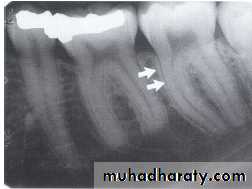

The maxillary sinus are paired cavities or compartments of bone located within the maxilla. The maxillary sinus are located above the maxillary permolars and molars teeth. Radiographically the sinus appears as a radiolucent area located above the apices of maxillary premolars and molars. The floor of sinus is composed of dense cortical bone and appear as radiopaque.

SEPTA WITHIN THE MAXILLARY SINUS:

Septa are bony wall that divided the maxillary sinus into compartment. Radiographically the septa appear as a radiopaque line within the sinus.

Nutrient Canals within Maxillary Sinus

Nutrient canals may be seen within maxillary sinuses. Nutrient canals are tiny, tubelike passageways through bone, which contain blood vessels and nerves that supply maxillary teeth and interdental areas. On a maxillary periapical image, a nutrient canal appears as a narrow radiolucent band bounded by two thin radiopaque lines.INVERTED Y